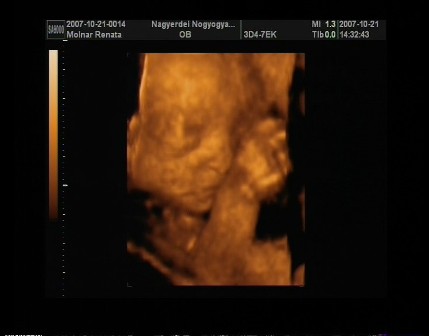

reni, na azt elhiszem hogy be vagytok már sózva az uh miatt!